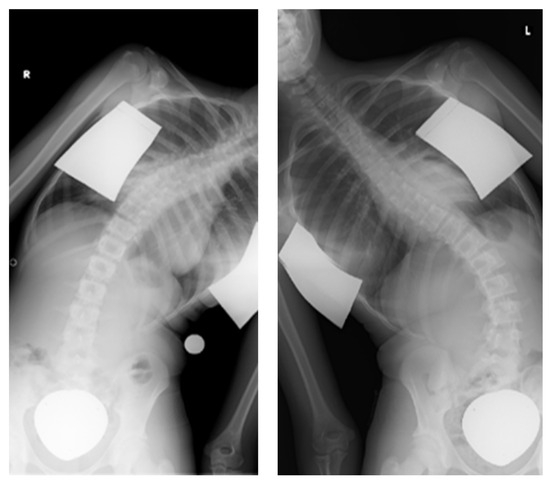

| 7 days | Distal ApiFix screw was too long | Replacement with a shorter screw |

| 3 months | Screw dislocation with lateralization of the implant | Implant replacement |

| 11 months | Scar tissue excision with subsequent infection and fistula on the caudal wound pole | Complete removal of implant |

| 16 months | Loosening of screws with loss of curve correction | Complete removal of implant |

| 19 months | Loss of curve correction | Correction of kite angle, implant replacement with longer implant including renewed intraoperative distraction |

| 21 months | Low-grade infection with Cutibacterium acnes | Complete removal of implant |

| 22 months | Low-grade infection with Cutibacterium acnes | Complete removal of implant |